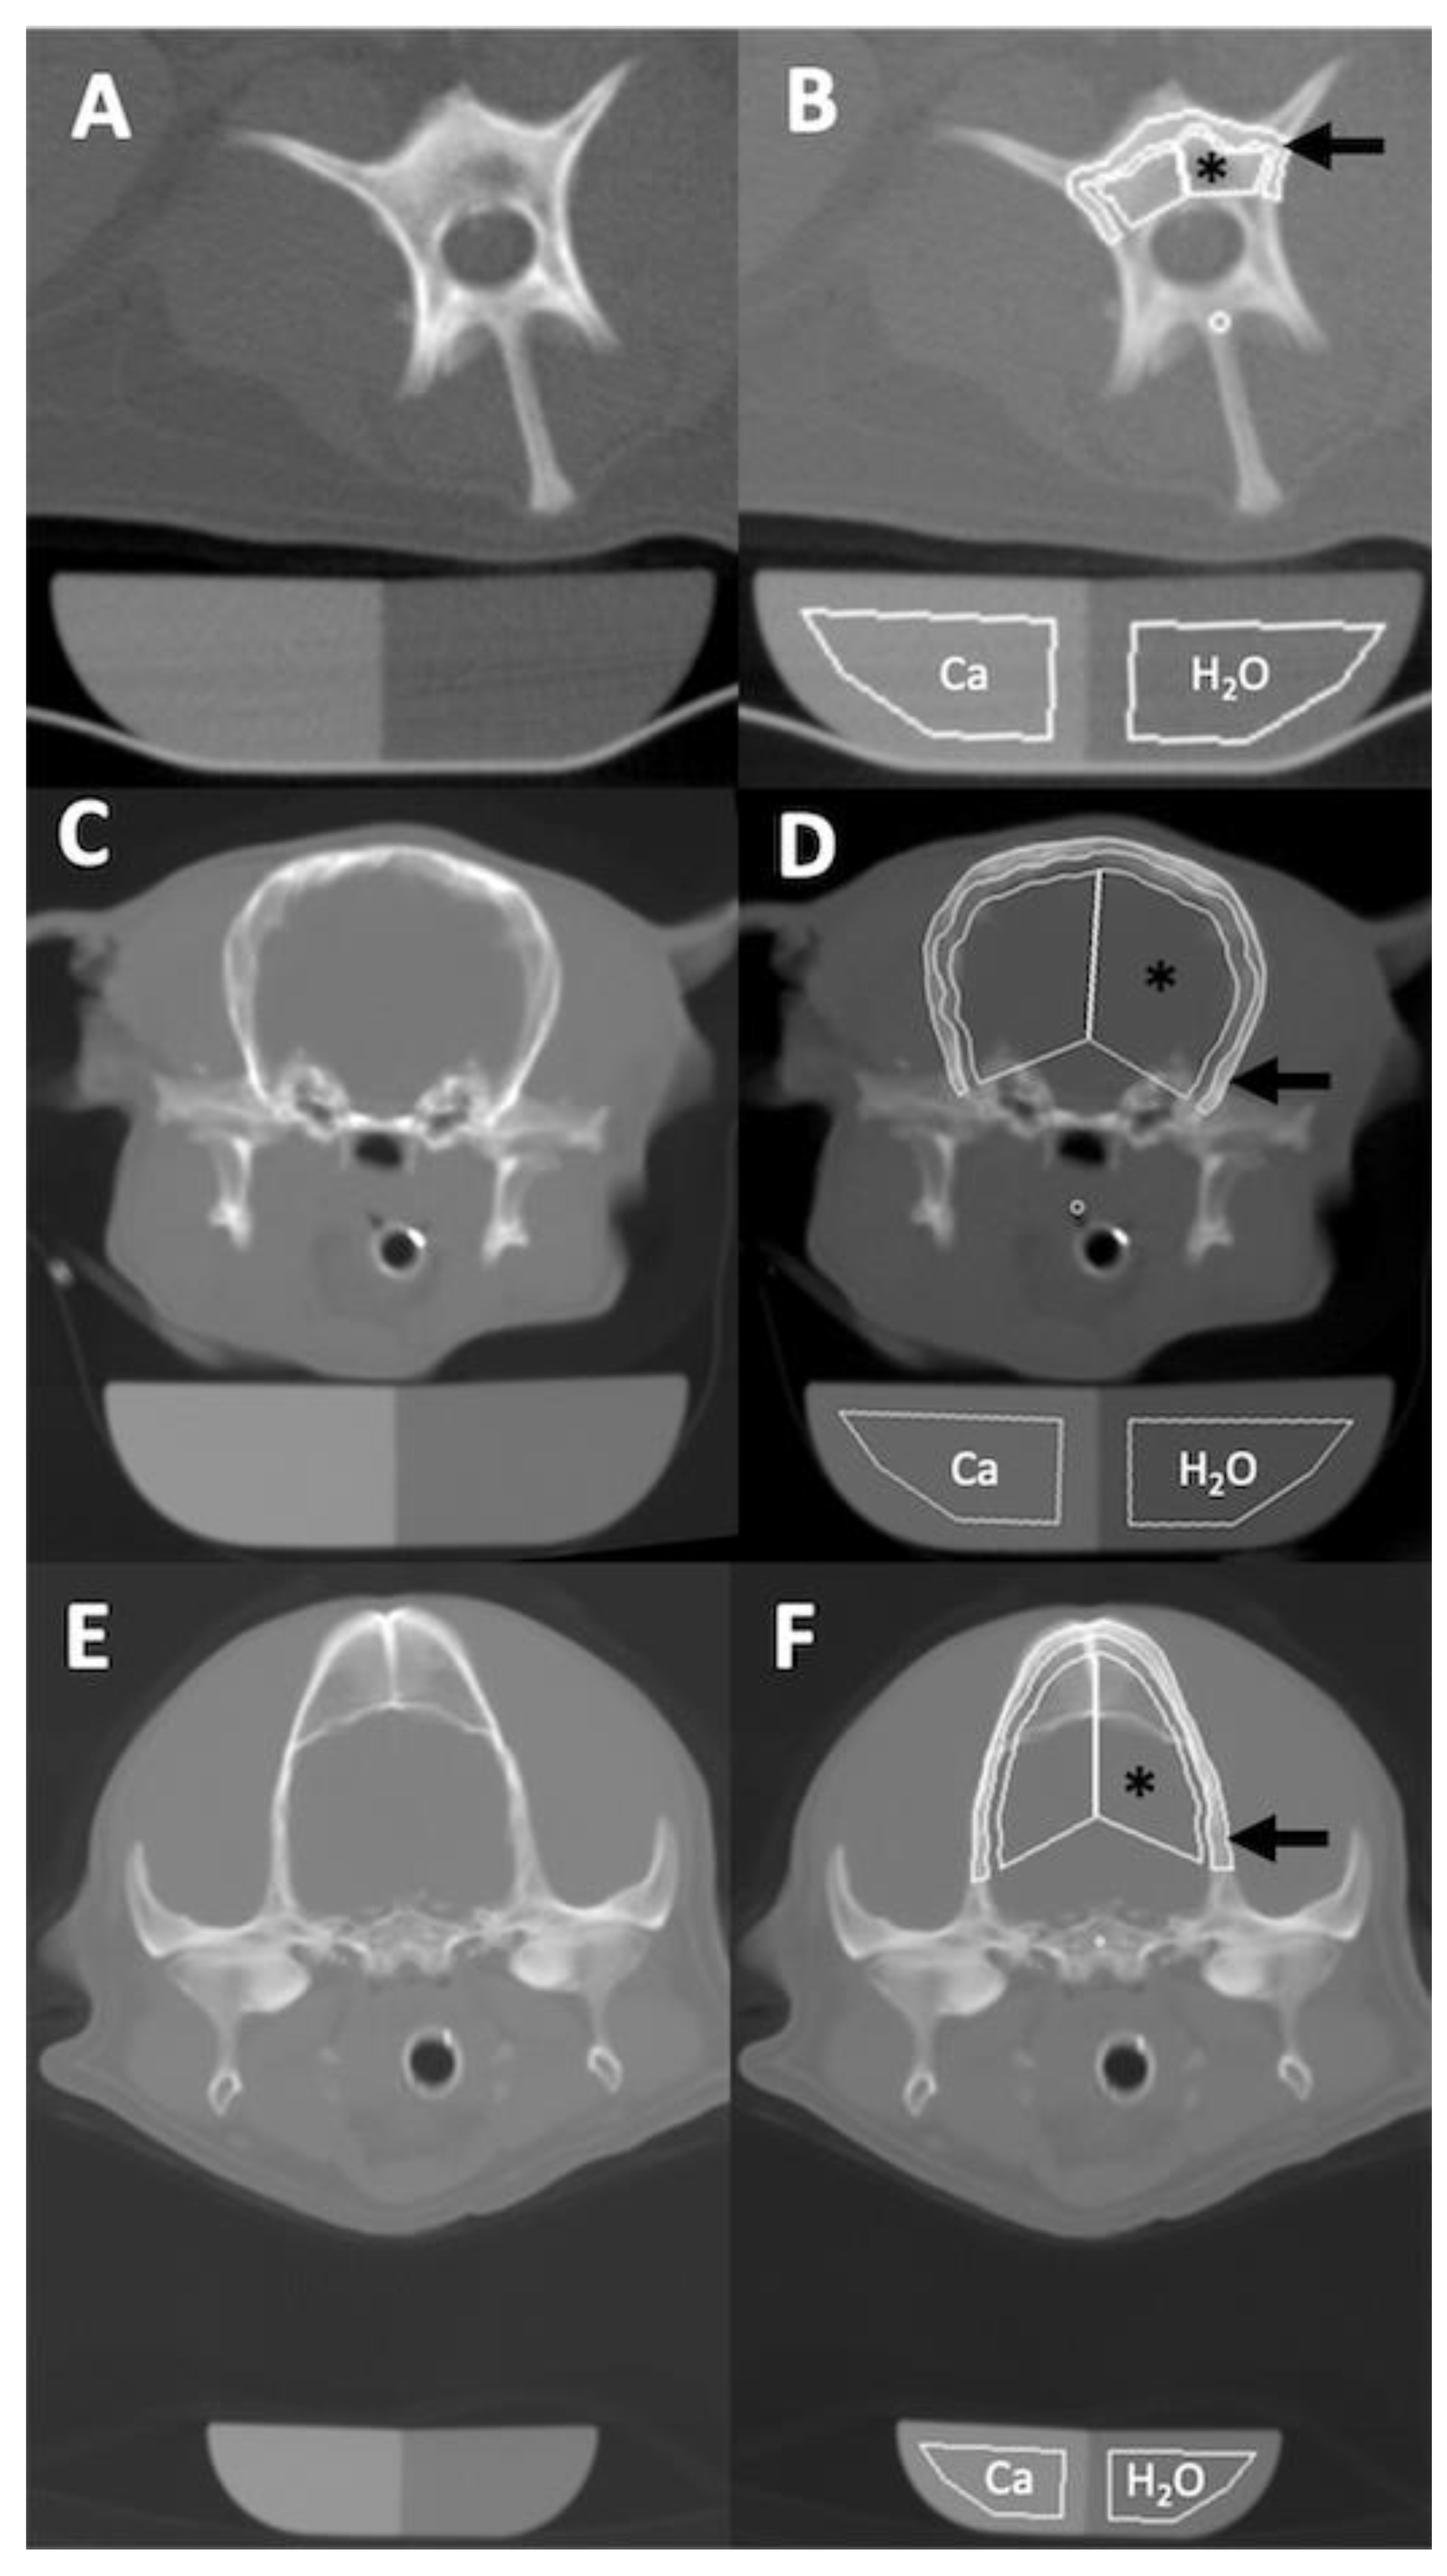

2.2. Quantitative CT Examination

3.2. Osteodensitometry Procedure

3.3. Bone Mineral Density Analysis